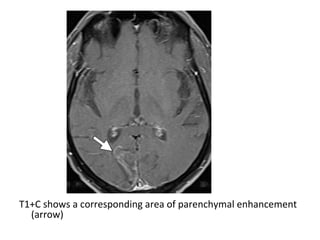

T1+C shows a corresponding area of parenchymal enhancement

(arrow)